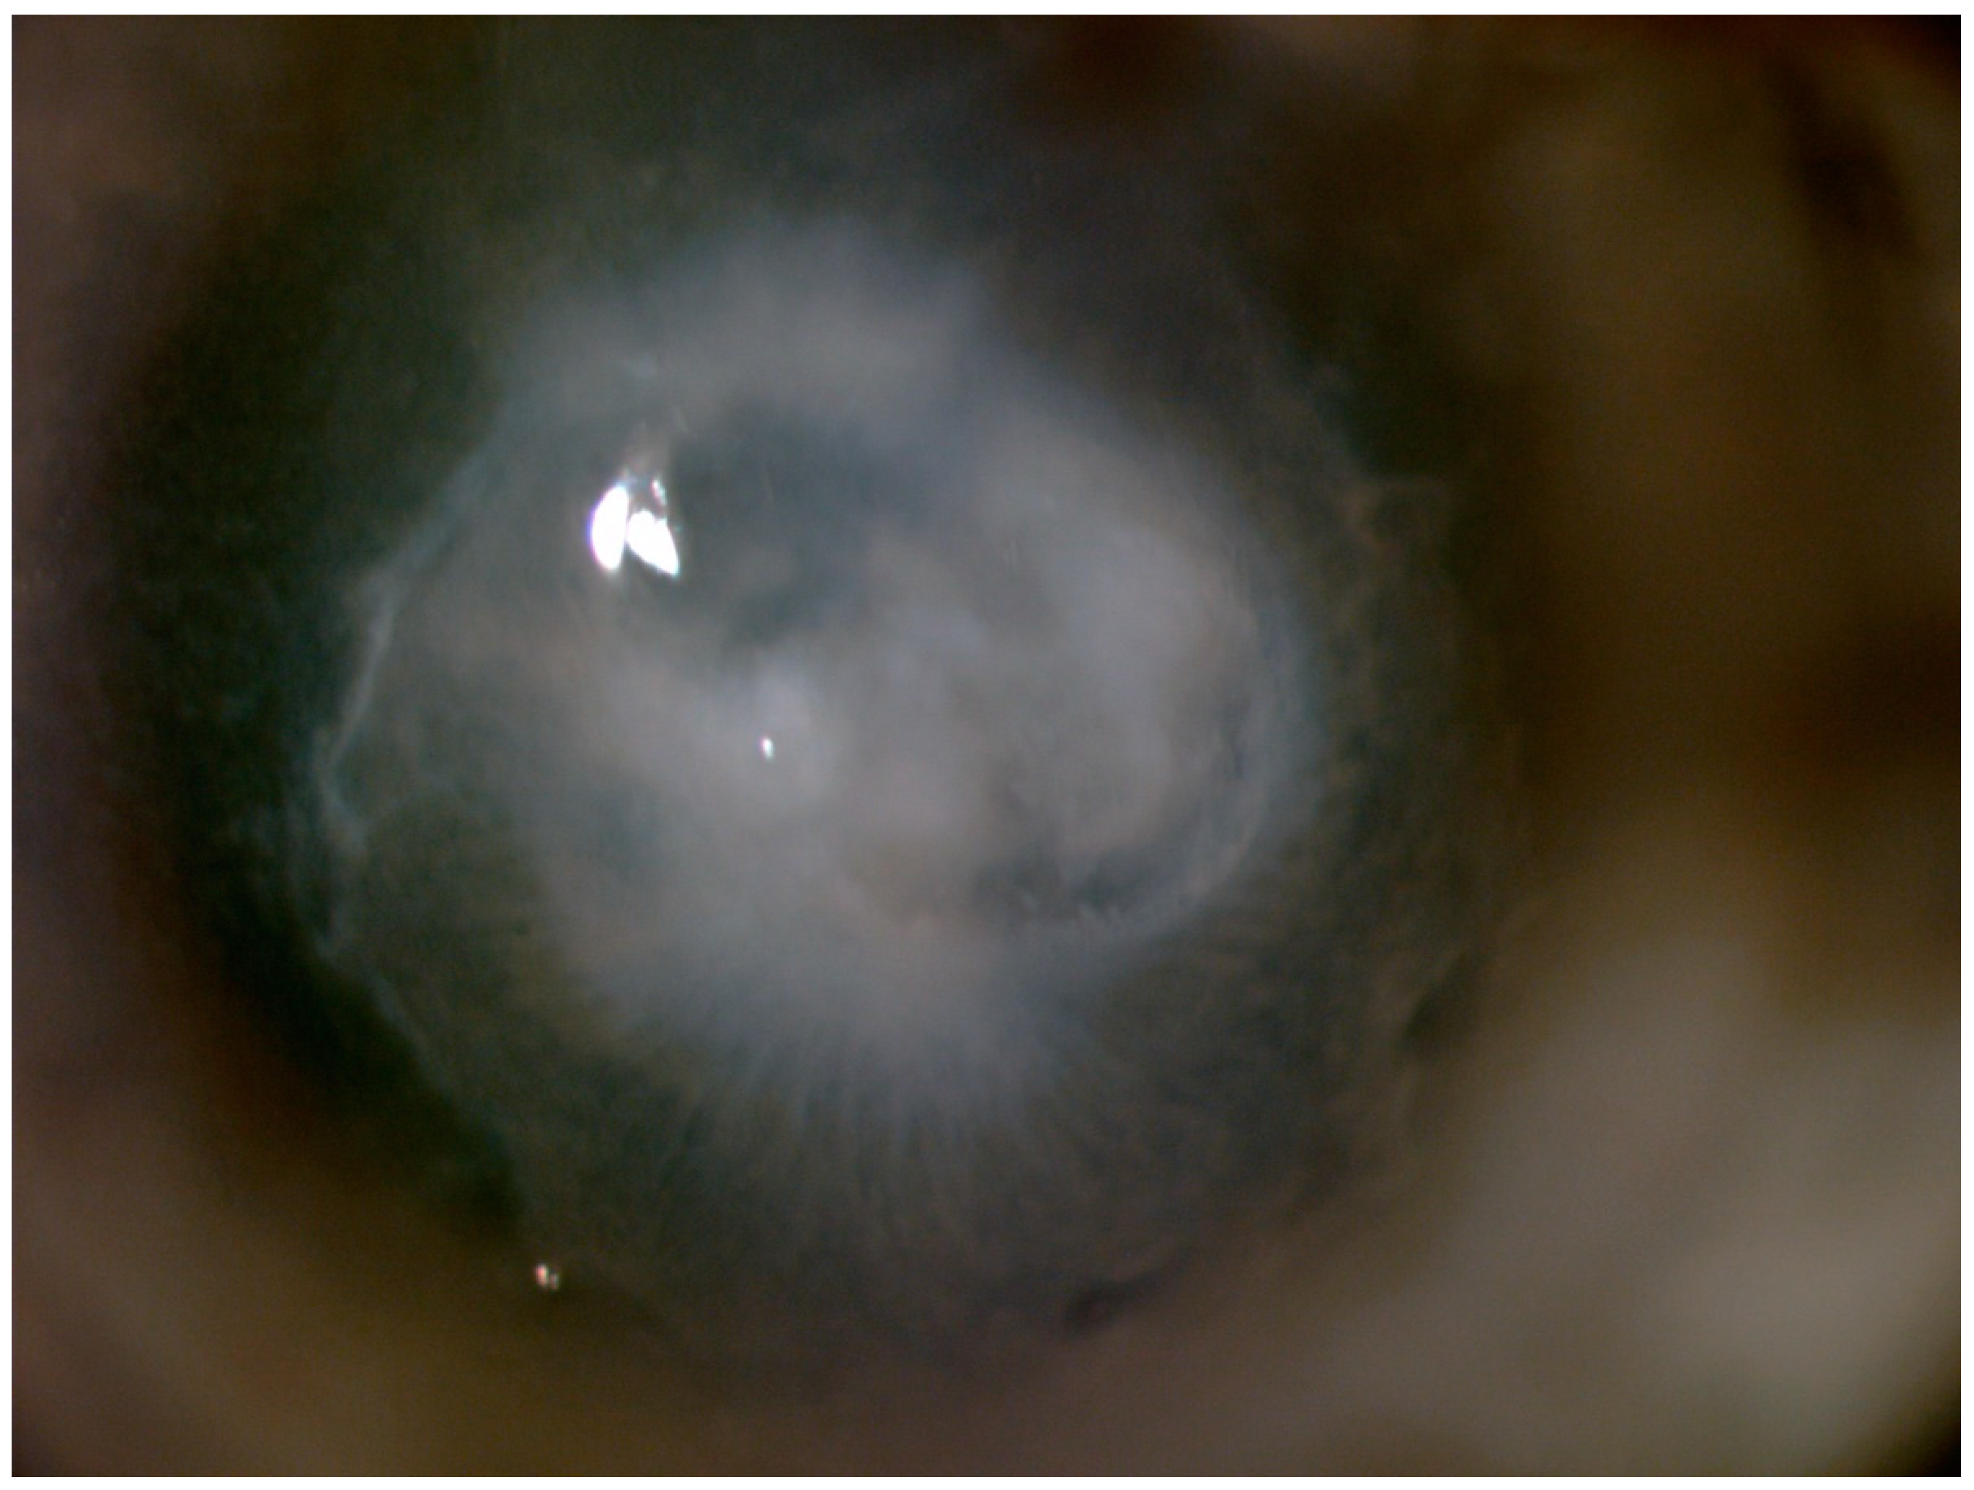

3. Results